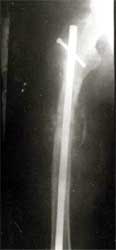

股骨骨折,钢板固定后失败。改用带锁髓内钉固定,4个月后骨折愈合。

肱骨骨折,3次钢板和钢丝固定后失败。改用带锁髓内钉固定,4个月后骨折愈合。